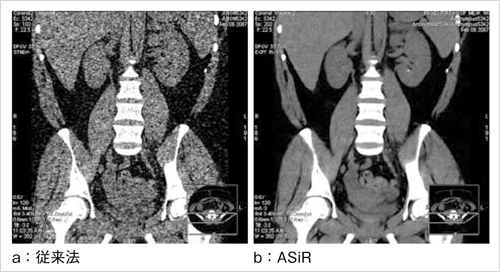

CTC検査では,空気(最近では被検者の苦痛軽減のため,炭酸ガスを用いる施設もある)を注入して大腸を拡張させ,仰臥位と腹臥位の2回のCT撮影が一般的である。ポリープ描出のみが目的であれば,線量を下げての撮影も可能であるが,壁肥厚状態を診断するにはアキシャル像も読影する必要があり,画質の劣化は看過しがたい。被ばく低減が世間の関心を集める中,いかに被ばくを減らし,良質な画像を維持できるかもCTC検査の普及にかかわってくるであろう。GEのCT装置は,画像再構成技術“ASiR(Advanced Statistical Iterative Reconstruction)”を搭載することで,従来の画質を保ちながら被ばくを40%まで軽減することを可能にした(図4)。

図4 ASiR画像再構成法

生データに含まれるノイズを算定するために,統計学的手法を用いて画像の再構成を行い,CT値を正しく算出する。従来の画質を保ちながら,被ばくを40%まで軽減することを可能にした。